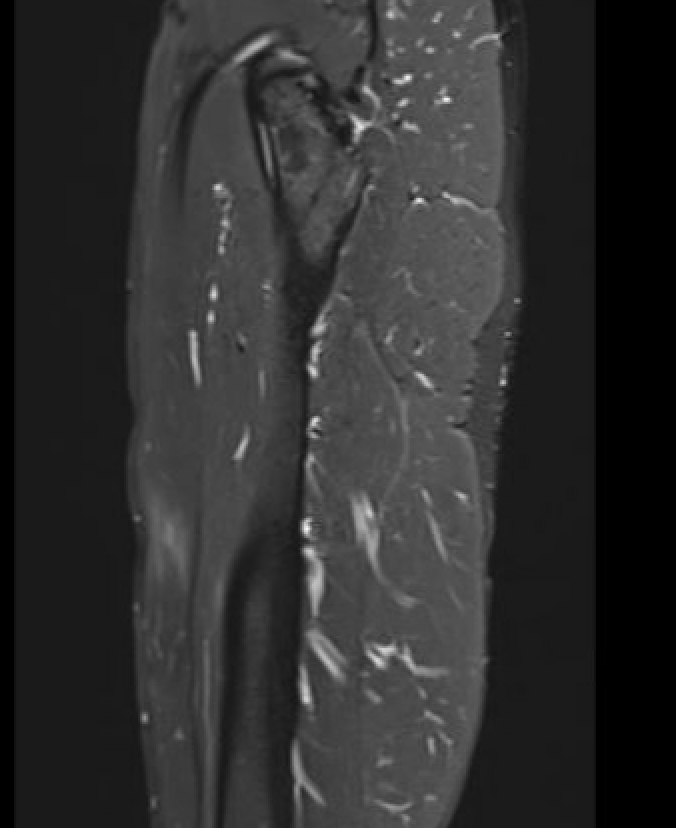

Chronic Grade 4 proximal rectus tear

Grade 4B Rectus femoris musculotendinous injuries